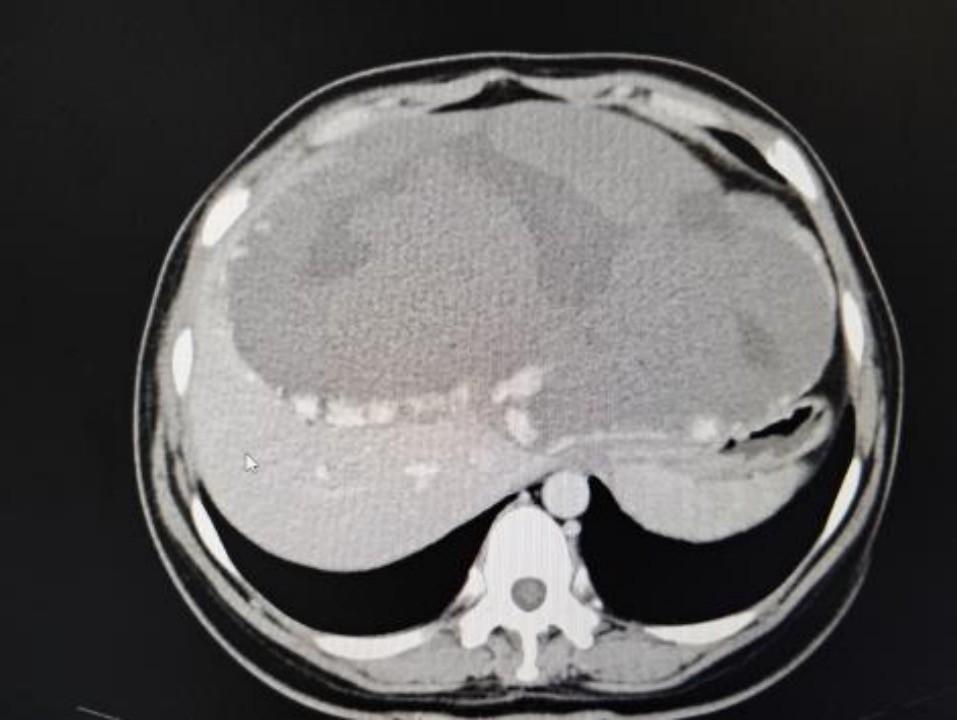

肝脏中常见的良性肿瘤——肝血管瘤,通常不威胁生命健康。但若肿瘤体积增至30cm×24.4cm×14.6cm,则会严重损害血液循环,压迫周边器官,并带来生命危险。李女士的病例生动地体现了这一罕见疾病的典型症状。

肝血管瘤主要因肝内血管过度扩张与生长所致。李女士的肿瘤体积大幅增长,濒临突破常规解剖限制,几乎触及腹腔容量上限。此巨型肿瘤不仅侵占腹腔空间,还对胃、肠等邻近器官施加压迫,不仅损害其功能,更可能引发器官移位或变形,进而加剧患者不适。

巨瘤对血流动力学产生显著扰动。肿瘤内部血管分布失衡,流速提升,这不仅加剧了肿瘤增大,且可能引发肿瘤破裂及出血,对患者生命构成威胁。因而,对于李女士而言,肿瘤不仅构成了生理上的负担,更是潜在的生命危险源。

经过周密策划与预案审核,由杨诏旭副主任领衔的包括范明、张小晶、郝晓坤、刘海旺等在内的医疗小组,迅速投入到一台极具挑战性的手术中。术中,在患者腹部壁下方成功建立了观察窗,内窥镜观察发现腹腔几乎被巨型血管瘤完全占据。因第一肝门受到严重压迫,手术区域非常狭小。

巨型血管瘤内充血液,外围环绕着丰富的血管网和连接肝组织的分支。手术过程中,需在狭窄空间内细心、准确地逐段辨认并结扎肿瘤周边的血管。此过程对施术者的耐力与精确度极为关键,任何失误都可能导致大量出血。